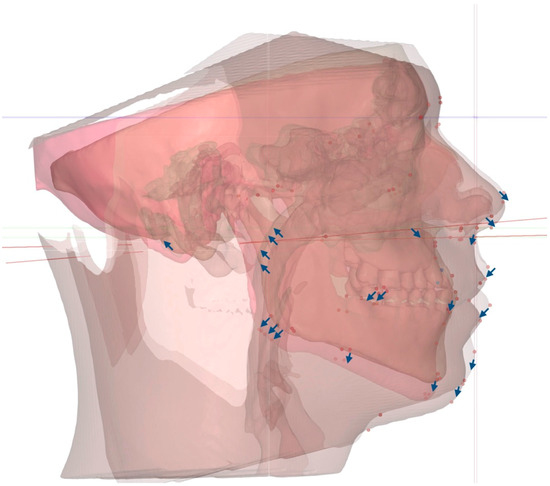

Background/Objectives: Mini-Screw-Assisted Rapid Skeletal Expansion (MARPE) appliances have been widely used for maxillary skeletal expansion in non-growing subjects and adolescents with a fused midpalatal suture. The current case report describes the immediate 3D cephalometric changes in the skeletal and soft tissue parameters, [...] Read more.

Background/Objectives: Mini-Screw-Assisted Rapid Skeletal Expansion (MARPE) appliances have been widely used for maxillary skeletal expansion in non-growing subjects and adolescents with a fused midpalatal suture. The current case report describes the immediate 3D cephalometric changes in the skeletal and soft tissue parameters, along with upper airway volume, shape, and dimensions, in a patient with Skeletal Class I anterior underbite. Methods: The pre- and post-expansion full-face Cone-Beam Computed Tomograms (CBCTs) of a 19-year-old patient who underwent 3D-guided midpalatal piezocorticotomy-assisted MARPE were compared and analyzed using 3D cephalometric software. Both CBCT volumes were re-oriented relative to the Frankfurt horizontal plane (FHP) to accommodate postural changes. Results: The total upper airway volume and minimum upper airway cross-section increased after expansion. The nasal base plane (ANS–PNS) rotated in all three spatial planes, including the sagittal plane (anterior downward and posterior upward rotation, with the center of rotation around the maxillary center of rotation) and the vertical plane (upward rotation on the left side). The maxillary canine and molar cant planes rotated around the center of rotation in the midface, with left upward and right downward rotation. The orientation of the ANS–PNS plane changed due to the leftward rotation of the ANS, with the center of rotation approaching the PNS. Cervical curvature improved from kyphotic to lordotic immediately following expansion. Conclusions: Three-dimensionally guided midpalatal piezocorticotomy-assisted MARPE has been shown to produce midfacial changes in all three spatial planes when evaluated via 3D cephalometric analysis. Comprehensive observational studies are necessary to analyze these changes and their effects for different skeletal classifications. Full article